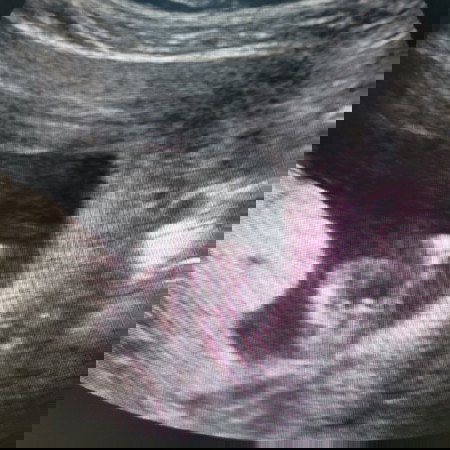

พอดีไปซาวมาครบ 13 สัปดาห์ ไม่ได้คิดว่าจะได้ลุ้นเพศ พอหมอซาวเจอท่านี้เลยครับ หมอเลยบอกน่าจะ ผช นะ แต่ยังไม่เฟิมครับ 70เปอเซนหมอให้ความเห็นว่าผู้ชาย เลยจะมาถามความเห็นคนอื่นๆครับ ถ้าทราบผลชัวแล้วจะมาแจ้งเพิ่มนะครับ ขอบคุณครับ

น่าจะชายน่ะค่ะ เหมือนมีอะไรโด่ๆ บ้านนี้ตอนซาว 13 วีค ก็เห็นแบบนี้ค่ะ ตอนนี้ 18 วีค หมอเฟิมว่า ผช ชัวร์ค่ะ ซาว 2 ครั้ง ก็โด่ๆแบบนี้ค่ะ

ผลเลือดจากนิฟออกแล้ว สรุปคือ ผู้ชายนะครับ ขอบคุณทุกคนที่ทายนะครับ

น่าจะชายจ้า ในภาพเห็นจู๋โด่ๆคะแม่